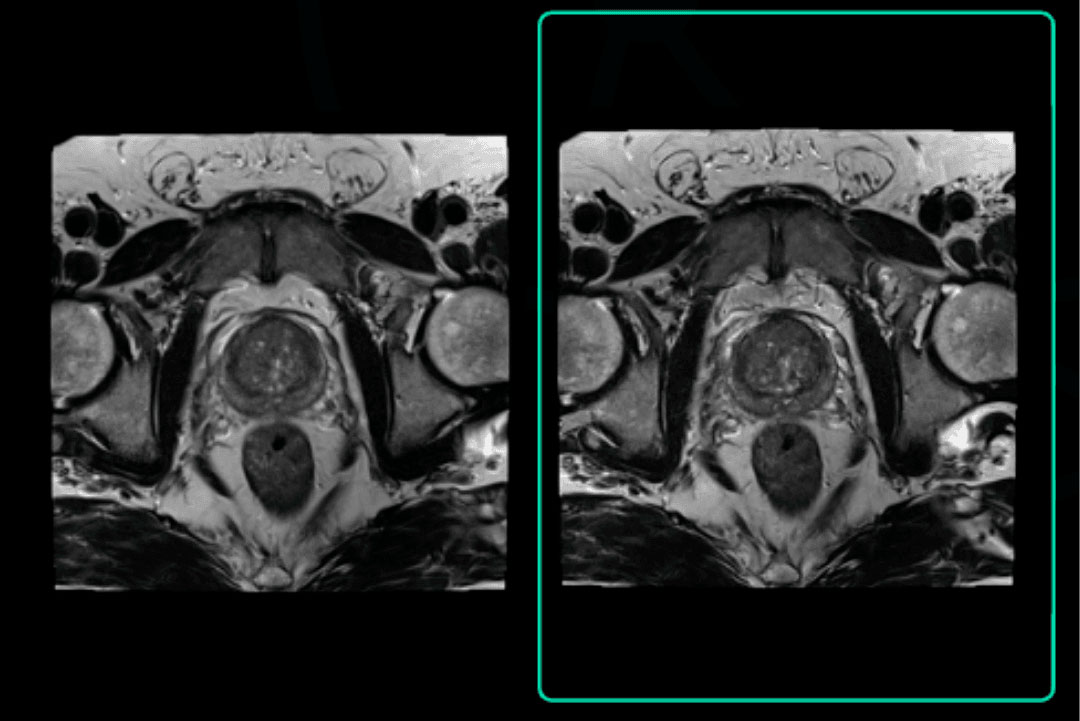

Varredura original: 3:46

Tempo Acq: 320×320

Varredura acelerada aprimorada por SubtleMR™

Tempo Acq: 1:29